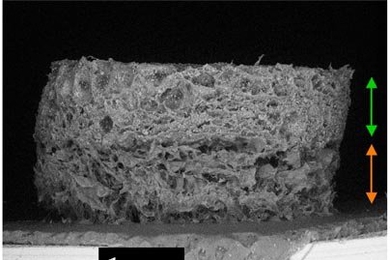

Wearable blood pressure sensor offers 24/7 continuous monitoring

Device could help diagnose hypertension, heart disease